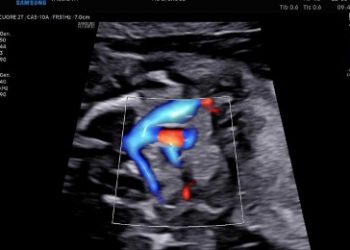

Cari soci, questo mese un nuovo video "How to do", sul corretto settaggio del Doppler in Ostetricia. Grazie a Paola...